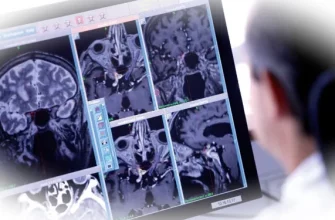

Для начала стоит разобраться, что же такое бруксизм и почему он возникает. Это непроизвольное, неконтролируемое сжатие или скрежетание зубами, происходящее во время сна. Причины его возникновения могут быть самыми разными — от стресса и тревожности до нарушений сна, неправильного прикуса и генетической предрасположенности. Независимо от первопричины, бруксизм наносит существенный вред зубам, суставам и мышцам лица, вызывая болезненные ощущения, воспаление и даже разрушение зубной эмали. К счастью, существует множество способов справиться с бруксизмом и предотвратить его негативные последствия. Диагностику и тактика лечения определяет специалист гнатолог, имеющий опыт практической работы, в том числе со сложными случаями: dsstudio-clinic.ru/service/gnatologija/.

Важно отметить, что лечение должно быть комплексным и учитывать индивидуальные особенности каждого. Только совместная работа пациента и квалифицированного стоматолога, гнатолога и невролога позволит выработать наиболее эффективную стратегию борьбы с этим недугом. Регулярные визиты к специалисту, соблюдение рекомендаций и приверженность к лечению — ключ к успешному преодолению бруксизма и восстановлению здоровья полости рта.